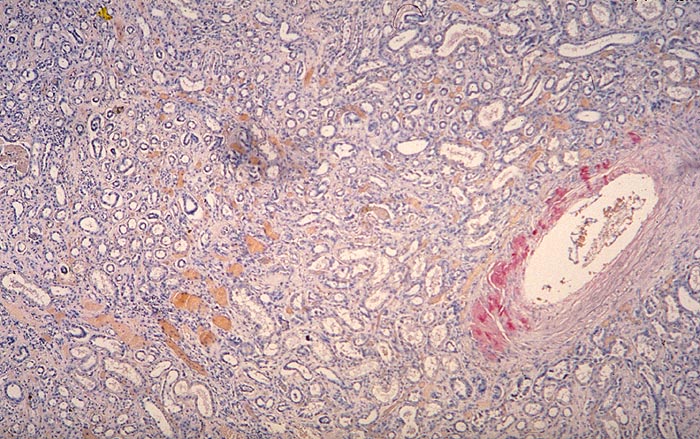

Amyloidose der Gefässe

Niere

Ausschliesslich Amyloidablagerungen in einer Arterienwand.

Glomeruli und Interstitium negativ. AL-Amyloid.